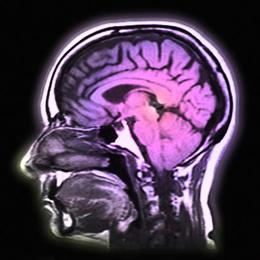

研究人员根据精神病患者大脑MRI成像数据和其后病情发展数据开发出了新算法

在英国医学研究委员会和维康基金会资助下,英国伦敦国王大学和伦敦大学学院研究人员对上百名处于初期阶段的精神病患者进行大脑核磁共振扫描,并在其后6年持续跟踪,最终根据这些患者的脑成像数据和其后的病情发展数据,开发出了一种新算法。通过该种算法对处于初期阶段的精神病患者脑成像数据进行分析,能够区分出哪些病人会发展成持续性精神病,而哪些病人会发展成间歇性精神病。